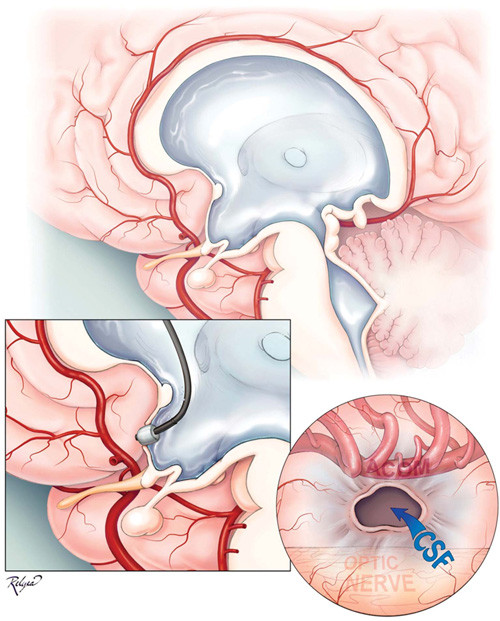

Vậy căn bệnh não úng thủy mà Quốc vương Thái Lan đang mắc là bệnh như thế nào? Não úng thủy xuất hiện do tình trạng dư thừa một loại chất lỏng trong não còn gọi là dịch não tủy (DNT). Sự dư thừa này dễ làm đầu bệnh nhân có dấu hiệu to dần, làm nhu mô não bị tổn thương.

Bình thường, DNT luôn hiện diện trong não, có tác dụng giảm các sang chấn tác động từ bên ngoài vào. DNT được bộ phận rối mạch mạc tiết ra và được bộ phận khác có tên Pacchioni lấy đi.

Hiện tượng dư thừa DNT bắt nguồn từ việc đám mạch mạc tiết ra quá nhiều hoặc do các thể Pacchioni hấp thu kém. Việc đám mạch mạc tiết ra quá nhiều trong khi các thể Pacchioni hấp thu quá kém cũng là nguyên nhân gây bệnh.